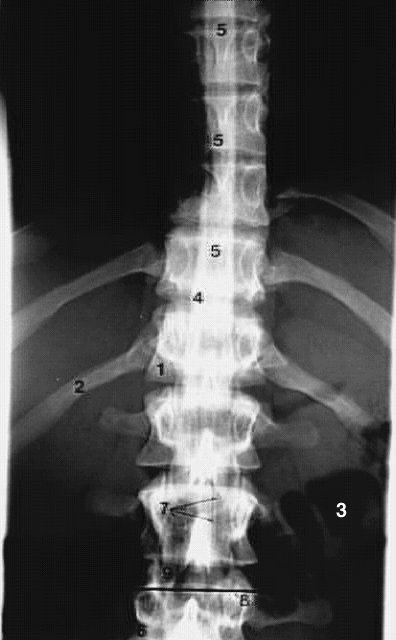

Back- Lumbar myelogram AP

1. 12th thoracic vertebral body

2. 12th rib

3. Air in colon

4. Contrast in subarachnoid space

5. Spinal cord

6. L3 body

7. Nerve rootlets (cauda equina)

8. Plane of Back-CT

9. Intervertebral disc.